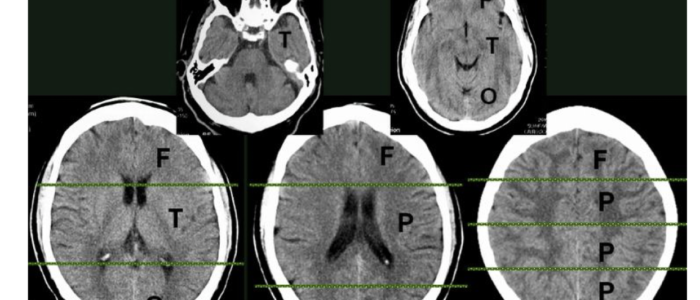

NeuroRadiology Booklet

Access here

Electronic booklet aimed for medical students and neurology residents, covers the basics of neuroradiology from the scratch.